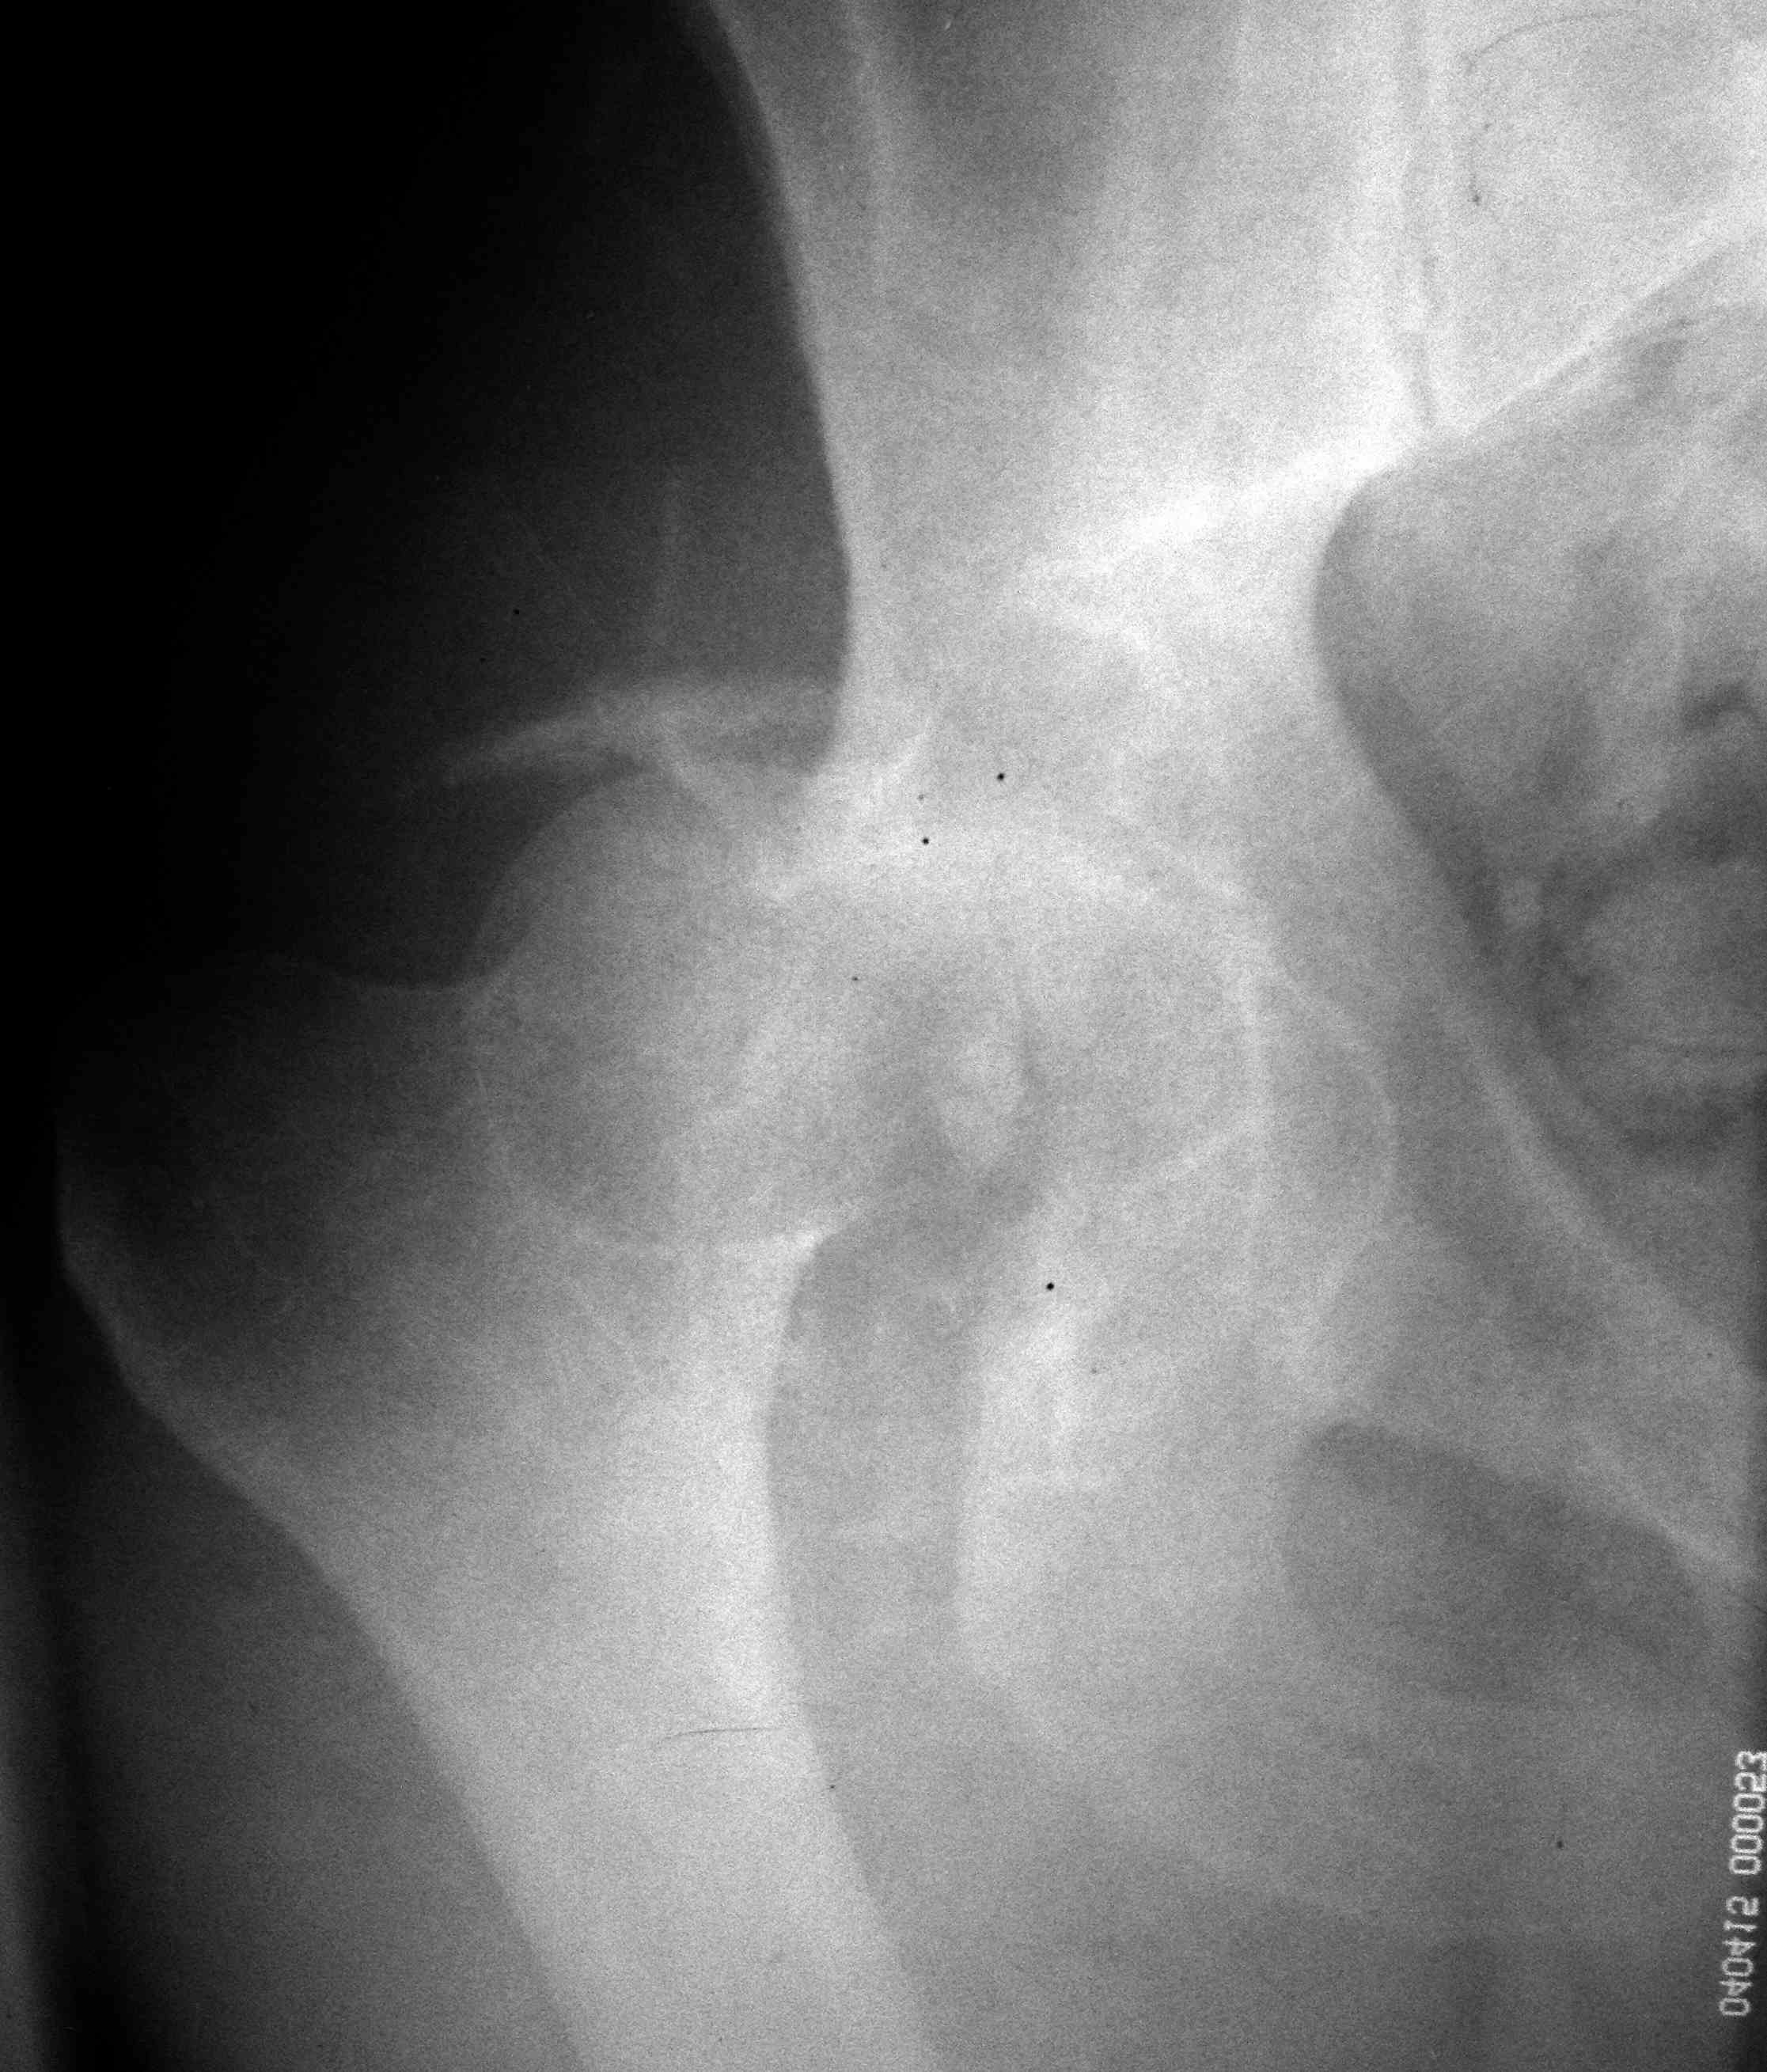

скан, который, на мой взгляд наиболее интересен

На голени приемлемую репозицию можно сделать закрыто. Фиксация может быть спицами и аппратом или винтами и аппаратом (разгрузка сустава). На бедре для полноценного восстановления функции необходима артротомия и остеосинтез (доступ Кохера, похоже фрагмент заднего края вертлужной впадины).

Фрагмент в полости тазобедренного сустава большой. Мы бы оперировали. В похожем случае, но уже у нас, (см. приложение) внутрисуставной осколок был значительно больше предполагаемого.

Никита, фрагмент в вашем случае несколко в иной локализации и он реально "пережует" впадину, здесь он в ямке.

первым этапом сделали синтез задней стенки, дистракционный аппарат на ногу, снимки низкого качества, завтра постараюсь приложить нормальный рентген и КТ

Добрый день, коллеги! Повреждение вертлужной впадины вероятнее всего 62-А1.2 чистый переломовывих, оскольчатый перелом задней стенки, при этом внутрисуставной фрагмент, является частью артикулирующей поверхности ацетабулюм, а следовательно его необходимо извлечь и поместить на место, иначе мозаика может не собраться. Про FAI временно можно не вспоминать (не до него), поскольку наиболее тяжелое повреждение голени требует адекватного вмешательства.На представленных рентгенограммах таза после операции все отлично, полную картину даст КТ.